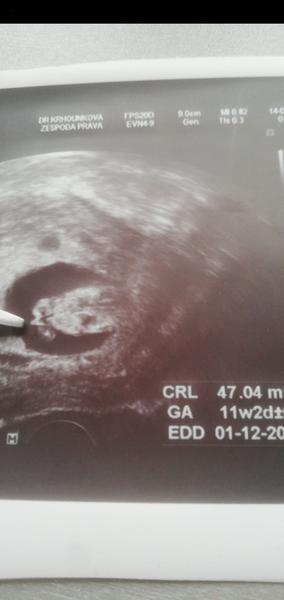

Ahoj holky, ta jsem se po X letech konečně poprvé zaregistrovala vždy jsem jen projížděl diskuze jako neaktivní člen, tak mam radost ze mohu byt konečně mezi Vami❤️jinak my mame termín 25.11-1.12 a jsme 11tt včera byla kontrola a odebrani krve na prvotrimestrální screening ktery nas čeká příští pátek, doktorka mi dokonce rekla i pohlaví což me trochu zarazilo, přiznám se ze jsem zadržovala slzy jelikoz jsem si přála vysněnou holčičku a na ultrz. Byl zvoneček 😄😄ale dnes jsem uz happy protože malej (4)bude mít bráchu a je to pro něj to nejlepší co může být ❤️

Ahoj holky, já se hlásím po prvním úspěšném screeningu a vše naprosto v pořádku 😘 gratuluji těm, které to mají také za sebou a už ví i dokonce pohlaví. My máme doma 3 letou princeznu a vypadá to, že k ní přibyde bráška 😍 ale ještě na to úplně nespoléhám, uvidíme až to půjde opravdu vidět. Spíš si pan doktor tipnul 😃